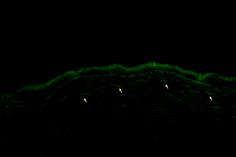

TUNEL阳性细胞在Epi-LASIK与LASEK术后4小时至3天均有较高表达,在术后1天均达到最高峰(见图2、3)。Epi-LASIK与LASEK组术后4小时、24小时、3天和1周的高倍镜下平均TUNEL阳性细胞数与对照组相比,差异有统计学意义(P<0.01);且在该四个时间点Epi-LASIK与LASEK组间相比显示Epi-LASIK有更轻的促凋亡反应,差异亦有显著统计学意义(P<0.01)。

图2 Epi-LASIK术后24h角膜TUNEL染色